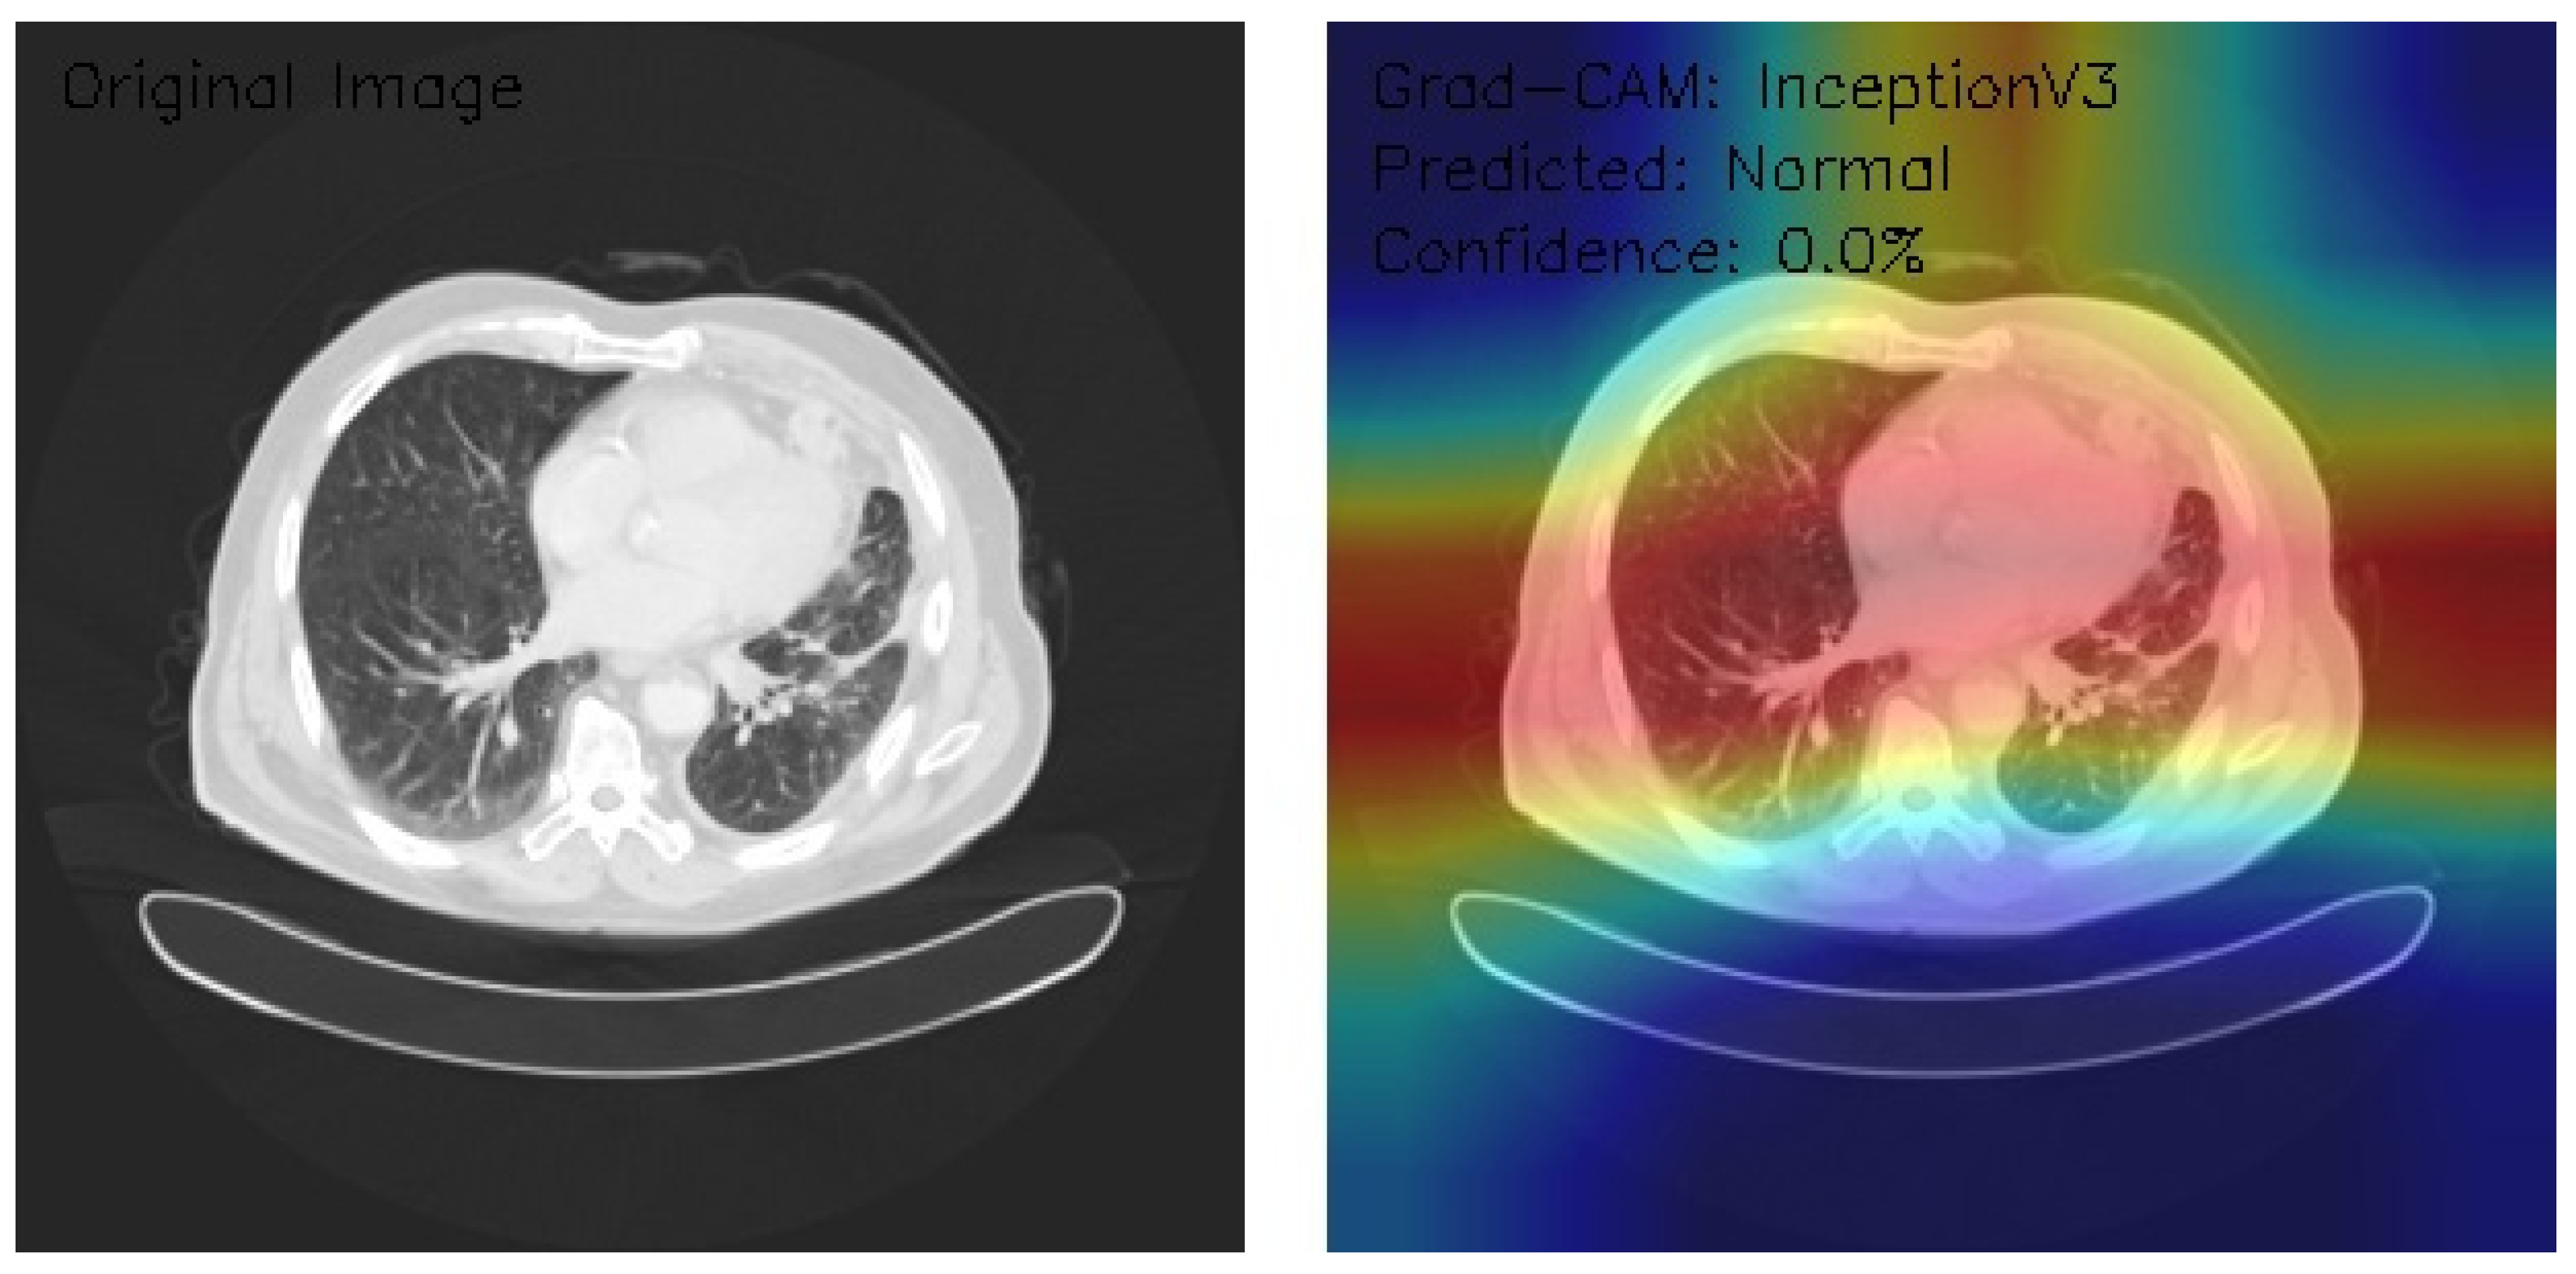

Analysis of InceptionV3 Model Performance on Lung CT Images with Grad-CAM Visualization

The results section of this study presents the detailed findings from an advanced analysis of three axial chest CT images processed using the InceptionV3 deep learning model. This analysis leverages the sophisticated capabilities of Grad-CAM to provide a comprehensive visualization of the regions within the CT images that the model identifies as significant for its predictions. Combining the robust classification performance of the InceptionV3 architecture with the interpretability offered by Grad-CAM, this approach not only evaluates the model’s predictive accuracy but also elucidates the spatial patterns of attention within the medical imaging context. This dual focus allows for a deeper understanding of the diagnostic potential of deep learning in radiology and the interpretive transparency essential for clinical application. The following results detail these observations, highlighting key insights into the model’s behavior and implications for automated diagnostic processes.

Figure 11 shows that the CT image displays interstitial patterns, indicative of potential structural abnormalities. The Grad-CAM visualization highlights strong activation centrally and in the right lung, with an asymmetric attention distribution favoring the right hemithorax. Despite this focused feature analysis, the model classifies the image as Normal with a confidence score of 0.0%, suggesting significant limitations in the model’s confidence calibration and decision-making reliability. The mismatch between observed features and classification confidence underscores the need for model refinement, particularly in aligning activation insights with robust, actionable predictions.

Figure 11.

This analysis evaluates three axial chest CT images processed by an InceptionV3 model with Grad-CAM visualizations, focusing on attention regions and classification outcomes. Image 1 shows clear lung fields with symmetric central activation, classified as Normal with 0.0% confidence. Image 2, with scattered nodular opacities, displays peripheral activation patterns and is classified as Malignant, again with 0.0% confidence. Image 3 exhibits interstitial patterns with strong central and right-sided activation, also classified as Normal with 0.0% confidence. The Grad-CAM visualizations highlight relevant anatomical features, but the model’s uniform low confidence scores reveal calibration and classification inefficiencies. Recommendations include the recalibration of confidence scoring, fine-tuning classification layers, and integrating ensemble methods. While feature detection appears robust, these refinements are critical for clinical reliability and decision-making.